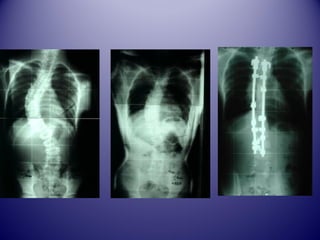

LLAA SSCCOOLLIIOOSSEE CCHHEEZZ

LL’’AADDOOLLEESSCCEENNTT

Définition ddee llaa SSccoolliioossee

 CC’’eesstt uunnee ddééffoorrmmaattiioonn

ttrriiddiimmeennttiioonnnneellllee ddee llaa

ccoolloonnnnee vveerrttéébbrraallee ddaannss

llee ppllaann ffrroonnttaall eett ssaaggiittttaall

aassssoocciiaanntt uunnee ddéévviiaattiioonn

llaattéérraallee eett uunnee rroottaattiioonn

vveerrttéébbrraallee aavveecc ggiibbbboossiittéé..

Traitement ddee llaa ssccoolliioossee::

PPrriinncciippee

 AArrrrêêtteerr llaa pprrooggrreessssiioonn ddee llaa ccoouurrbbuurree

((ccoorrsseettss))

 RRéédduuiirree llaa ccoouurrbbuurree ((PPllââttrree))

 CCoorrrriiggeerr llaa ccoouurrbbuurree ((CChhiirruurrggiiee))

 ÉÉvviitteerr lleess ccoommpplliiccaattiioonnss ttaarrddiivveess ((ccaarrddiioo--

ppuullmmoonnaaiirree,, nneeuurroollooggiiqquuee))

 AAmméélliioorreerr ll''eesstthhééttiiqquuee ((ggiibbbboossiittéé))

Traitement cchhiirruurrggiiccaall

 AArrtthhrrooddèèssee vveerrttéébbrraallee

ppoossttéérriieeuurr ((HHaarrrriinnggttoonn,,CCDD……))

 AArrtthhrrooddèèssee aannttéérriieeuurr

 AArrtthhrrooddèèssee tteemmppoorraaiirree

 EEppiipphhyyssiiooddèèssee vveerrttéébbrraallee

 CChhiirruurrggiiee tthhoorraaccoossccooppiiqquuee